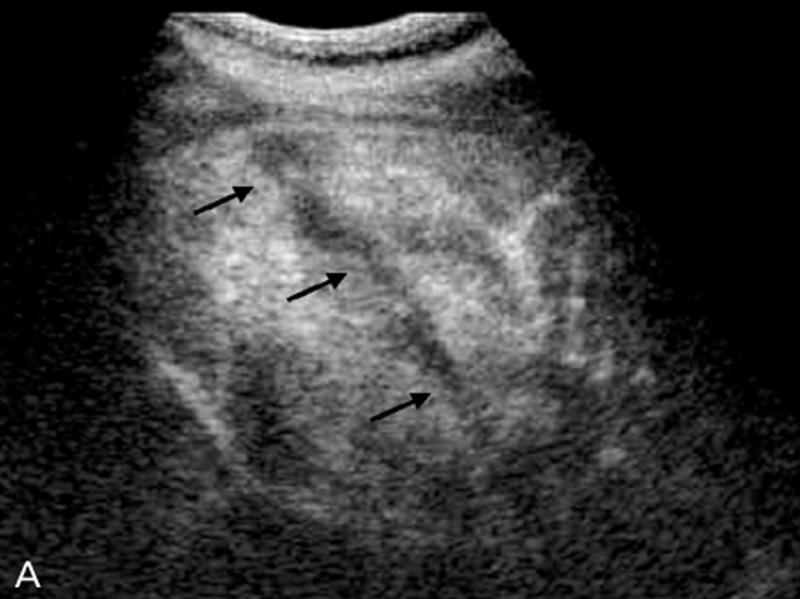

What is the sonographic appearance of Cirrhosis?

Hepatomegaly

Increased echogenicity and attenuation

Size

decrease of right lobe

Size increase of left and caudate

lobe

Nodularity

Fibrosis

Hepatospenomegaly

Ascites

Portal

hypertension

Hepatoma tumors

caudate lobe may be spared